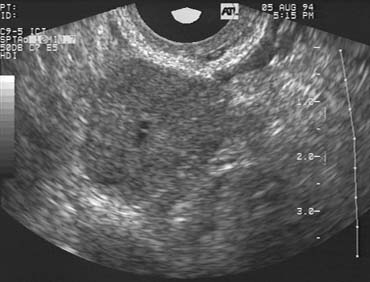

Chronic anovulation is a characteristic feature of polycystic ovarian syndrome (PCOS) and a common cause of infertility in affected women. The cause of the abnormal patterns of follicular growth, development, and regression typically observed in women with PCOS are poorly understood. Further research aimed at defining the mechanisms responsible for the aberrant patterns of follicular development in women with PCOS may, in turn, suggest new and more effective treatment strategies. Although the diagnosis of PCOS is based on clinical criteria (chronic anovulation, clinical or endocrinologic evidence of hyperandrogenism, and exclusion of related disorders), the ultrasonographic appearance of the ovaries in women with PCOS is also classic, if not specific for the disorder (Fig. 4).13

Fig. 4. (A, B) Ovaries with morphology typical of polycystic ovary syndrome. Note the peripheral location of many follicles in the 4 to 5 mm range in a characteristic string of pearls appearance.

Many women with PCOS present a difficult therapeutic challenge during attempts at ovulation induction. Whereas they often prove refractory to clomiphene treatment, women with PCOS also frequently exhibit an exquisite sensitivity to exogenous gonadotropin stimulation. The therapeutic range that will achieve progressive follicular development and ovulation but avoid frank superovulation of far more than a single ovum is often quite narrow. Consequently, serial TVUS examinations are essential to safe and effective treatment in women with PCOS.